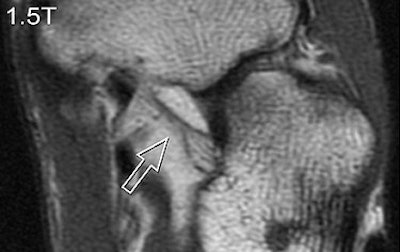

| A 31-year-old healthy male volunteer. Axial T1-weighted fast spin-echo images of foot show superior delineation of spring ligament (arrow) at 3 T (top and middle) as opposed to 1.5 T (below); 3.0TGR = 3.0T with GRAPPA algorithm. No significant difference was found between (top) and parallel (middle) acquisitions at 3 T; visualization of this ligament was rated very good at 3 T and as moderate at 1.5 T (below) by both radiologists. |

According to the results, GRAPPA MR resulted in a 44% reduction in scan time compared with conventional imaging. SNRs and CNRs doubled on the SPGR sequence at 3 tesla. These 3-tesla images also demonstrated comparable edge sharpness.

Image quality was rated highest on 3-tesla images. The axial T1-weighted sequence was given an average score of 3.4 at 3 tesla for parallel and normal acquisitions versus a score of 2.8 for 1.5 tesla. Visualization of ligaments and tendon abnormalities were also rated highly on parallel 3-tesla MR.